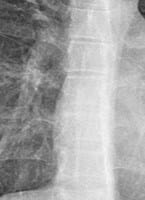

Cual es el tipo de mi escoliosis en es o en c